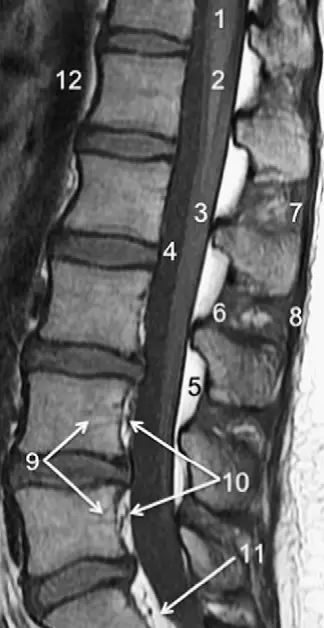

图1正常脊椎的MRI检查,左图为正中矢状位T2WI,右图为T1WI图 2 胸椎 T2WI 轴位图:1,肋椎关节;2,类骨头;3,黄韧带;4,椎弓根;5,椎弓板;6,横突;7,棘突;8,肋横突关节;9,肋结节;10,半奇静脉;11,后纵韧带图 3 腰椎矢状位 T1WI 序列成像:1,脊髓;2,脊髓圆锥;3,马尾;4,蛛网膜下腔;5,硬膜外脂肪;6,黄韧带;7,棘间韧带;8,棘上韧带;9,椎体静脉丛;10,硬膜外静脉丛;11,硬膜外脂肪;12 主动脉图 4 L5/S1 水平轴位 T1WI 序列成像:1,腰肌;2,L5 神经根(前支);3,L5 神经根(后支);4,黄韧带;5,蛛网膜下腔;6,马尾神经根;7,小关节面;8,髂腰韧带;9,左髂外静脉;10,左髂外动脉;11,右髂外动脉;12,右髂外静脉;13,多裂肌;14,竖脊肌组图 5 腰椎旁矢状位 T1WI 序列成像:1,腰静脉;2,腰动脉;3,椎间孔静脉;4,脊神经节后根;5,椎间孔静脉;6,关节面;7,多裂肌;8,竖脊肌群;9,胸腰筋膜,后层图 6 胸椎 T1WI 序列成像:1,胸髓;2,蛛网膜下腔;3,硬膜外脂肪;4,黄韧带;5,多裂肌;6,棘突;7,硬膜外静脉;8,棘上韧带图 7 胸椎矢状位 T2WI 序列成像:1,胸髓;2,蛛网膜下腔;3,黄韧带;4,多裂肌;5,棘突;6,棘上韧带;7,椎体静脉;8,脊髓圆锥;9,马尾图 8 胸椎旁矢状位 T2WI 序列成像:1,硬膜囊后壁;2,硬膜外脂肪;3,黄韧带图 9 胸椎轴位 T2WI 序列成像:1,主动脉;2,半奇静脉;3,奇静脉;4,椎间孔静脉;5,胸肋间血管;6,脊神经节后根;7,椎体静脉;8,后纵韧带;9,脑脊液流动伪影;10,多裂肌;11,背最长肌;12,斜方肌图10 胸椎旁矢状位 T2WI 序列成像:1,椎间孔静脉;2,胸椎旁肋间动静脉;3,神经根;4,上关节突;5,下关节突;6,关节面;7,椎弓峡部;8,椎弓根;9,黄韧带;10,竖脊肌群;11,斜方肌——本期完——